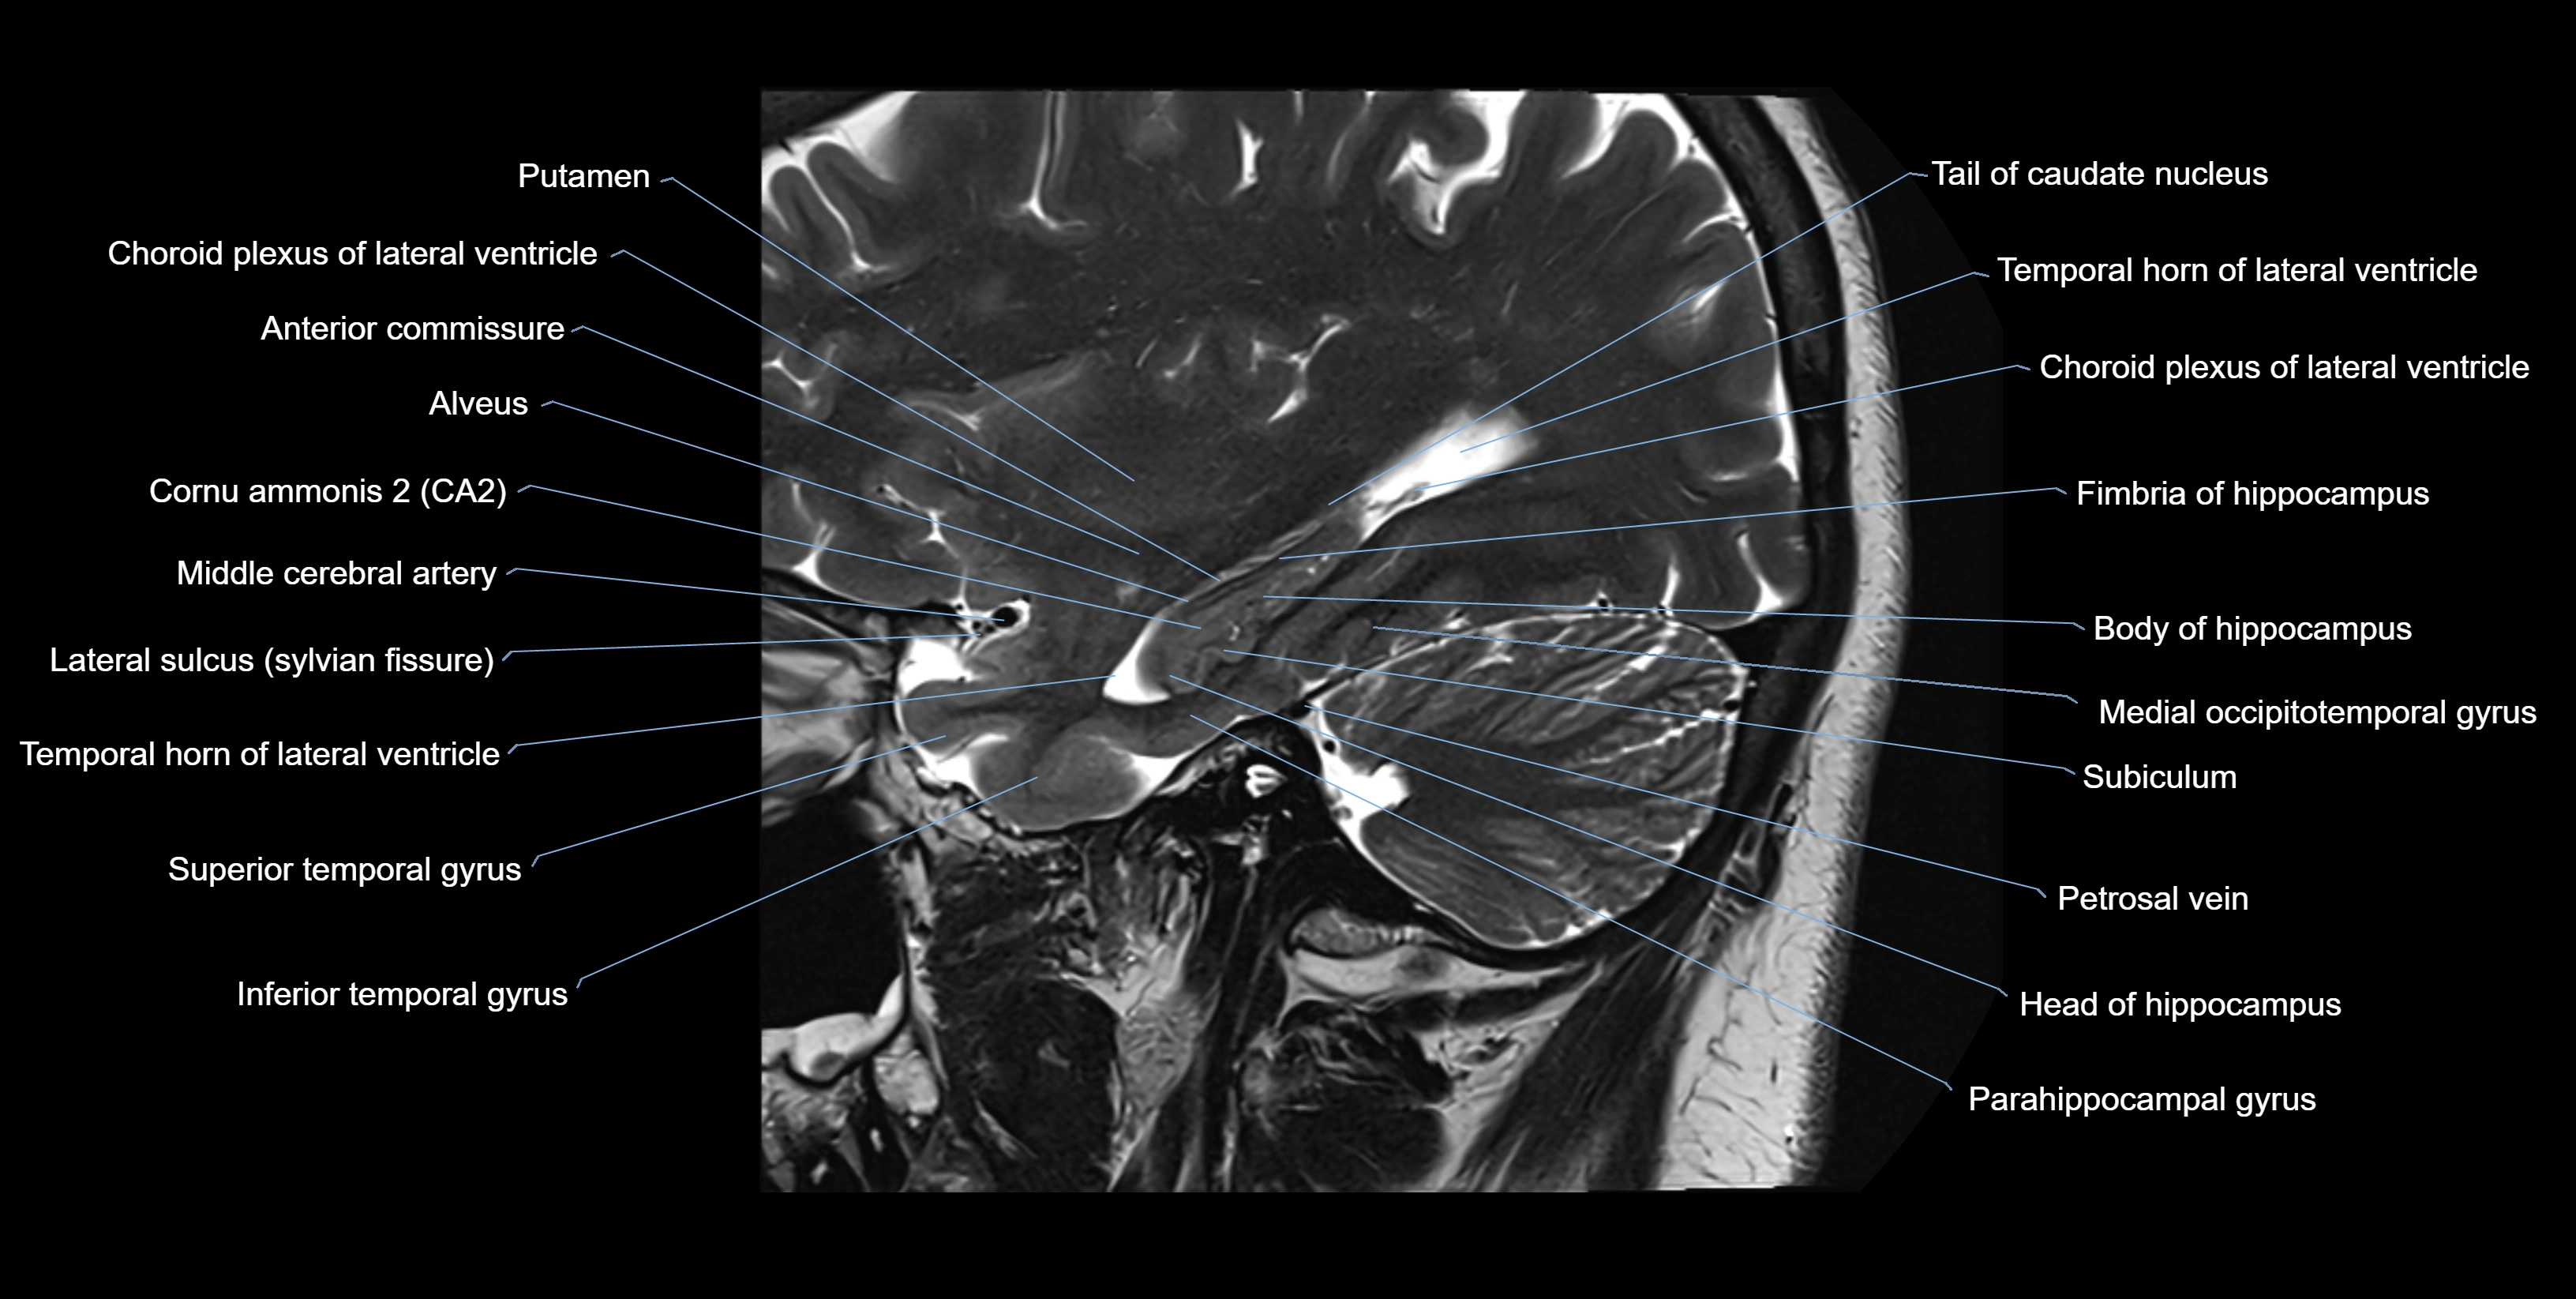

MRI images

image